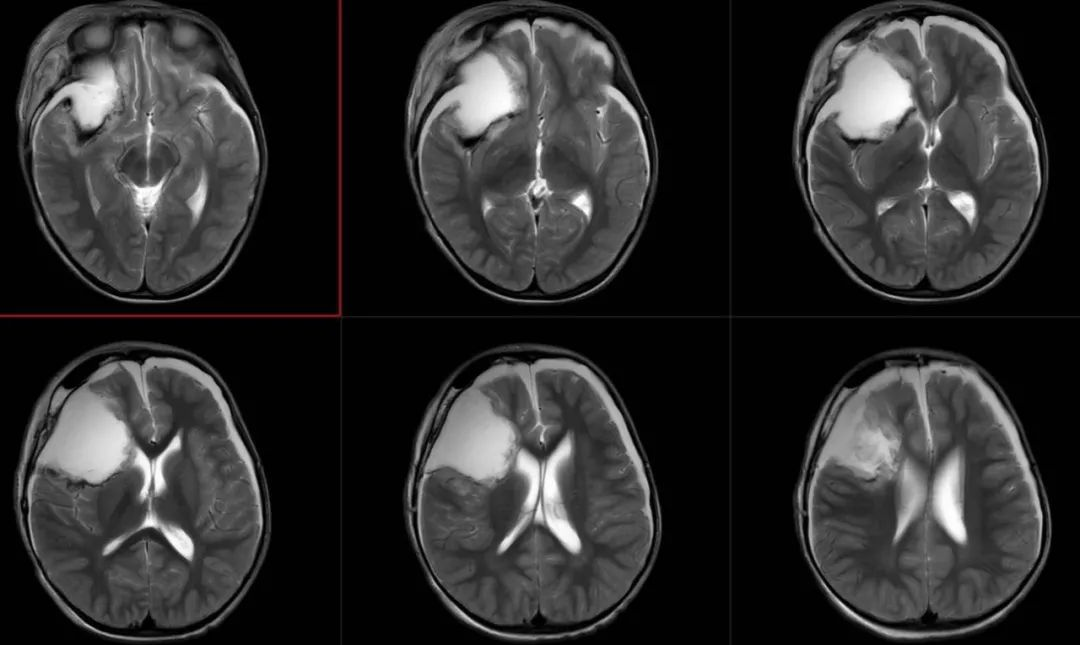

术前影像

术前FLAIR

术前T2轴位